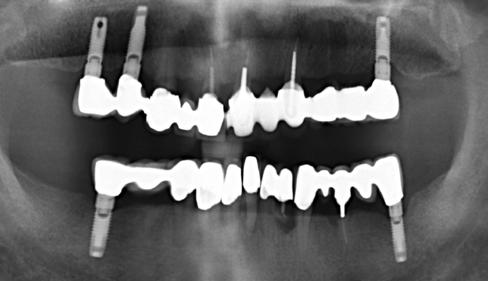

Egy 80-as éveinek elején járó páciens legfőbb panaszai a visszatérő fájdalom, diszkomfort érzés és a duzzadt, alsó szájképletek voltak. A vizsgálat mérsékelttől előrehaladottig terjedő csontvesztést mutatott ki a mandibula fogazatának esetében. Krónikus foggyökércsúcs gyulladásához társuló periapikális radiolucenciákat is diagnosztizáltak az alsó elülső szegmensben. Az alsó fogazatát a 3.7 és 4.7 fogak területein elhelyezett implantátumokon rögzített korona és hídpótlásokkal helyreállították 20 évvel ezelőtt. A rögzített hidak az implantátum felépítményeket és a természetes fogcsonkokon lévő koronákat kötötték össze (1. kép). A beteg egészségügyi kórtörténete nem volt lényeges.

1. kép: Sikertelen alsó fogpótlás és nagyon régi Steri-Oss implantátumok.

4. kép: A műtét előtti állapot – OPG.